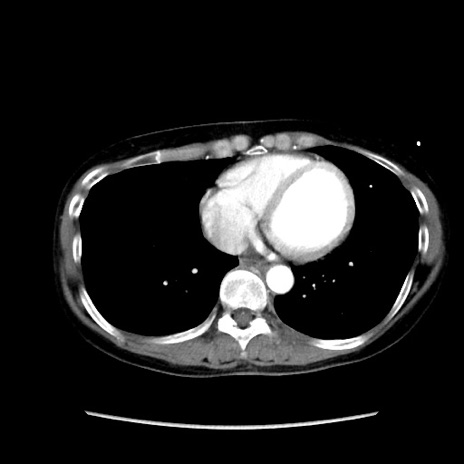

【症例】40歳代 女性

【主訴】上腹部痛、嘔気・嘔吐

【現病歴】約9時間前頃から急に上腹部痛、嘔気、嘔吐が出現。改善しないため救急要請。

【既往歴】子宮頚癌(広汎子宮全摘術、放射線療法)、腸閉塞

【身体所見】腹部:平坦、軟、腸雑音亢進、上腹部を中心に腹部全体に圧痛あり。

【データ】WBC 8400、CRP 0.03